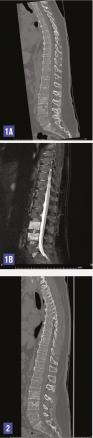

Cette femme de 46 ans avait des rachialgies mixtes évoluant depuis 3 mois sans fièvre, avec pour antécédents une chirurgie bariatrique et une ostéoporose densitométrique. L’examen clinique et le bilan biologique (dont des prélèvements bactériologiques) étaient sans particularité. Le scanner rachidien (fig. 1A) montrait une ostéolyse du plateau supérieur de L4 et une hypodensité du plateau inférieur de L3, et une prise de contraste et un hypersignal T2 des corps vertébraux et du disque à l’IRM (fig. 1B) compatible avec une spondylodiscite L3-L4. Les douleurs régressant à l’alitement et aucun germe n’étant trouvé à la biopsie discovertébrale, le diagnostic de spondylodiscite n’était pas retenu et la patiente était verticalisée avec le port d’un corset, sans complication. Deux mois plus tard, l’IRM montrait une nette régression de la prise de contraste L3-L4 avec néanmoins la persistance d’un hypersignal T2 au sein de la portion centrale du disque. Le scanner (fig. 2) montrant des phénomènes de reconstruction osseuse, le diagnostic retenu était celui de fractures des plateaux inférieur de L3 et supérieur de L4 dans le cadre d’une hernie intraspongieuse dans un contexte d’ostéoporose rachidienne.

La hernie intraspongieuse (nodule de Schmorl) est souvent asymptomatique mais parfois à l’origine de rachialgies mécaniques.1, 2 L’aspect à l’imagerie est celui d’une lacune arrondie hypodense communiquant avec le disque, limitée par la sclérose. En IRM, on peut noter un hyposignal T1 et un hypersignal T2 lié à la présence d’œdème osseux.1, 2 Parfois ces anomalies s’étendent à l’ensemble du corps vertébral et miment un processus tumoral ou infectieux. La scintigraphie osseuse, la tomographie monophotonique (SPECT), la tomographie par émission de positons ainsi que la biopsie osseuse sont alors utiles. C’est surtout le suivi de l’imagerie, avec disparition progressive de l’œ- dème en 3 à 12 mois, qui permet de conclure.2, 3